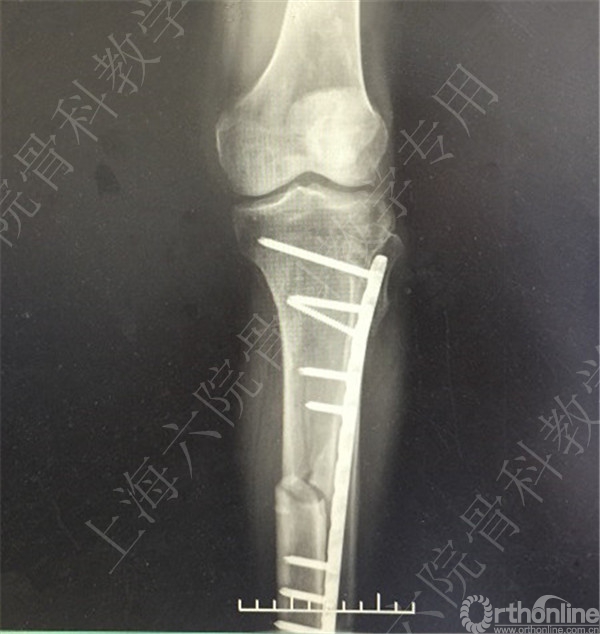

患者车祸伤至左胫腓骨开发性骨折,急诊予清除缝合+外固定术。

待软组织条件好转后,择期行右胫腓骨外固定拆除术+切开复位内固定术。

术后X线摄片示:骨折对位对线欠佳,稍成角。

患者复查,X线摄片示:骨折对位对线差,左胫骨立线欠佳,成角。

医方第一次跟换内固定术中,未纠正左胫骨立线,骨折对位对线差,未纠正成角,导致术后内固定失效,骨折成角变大。医方存在手术方式不当,手术操作不当,术后并发症观察、处理不当,对疾病评估不足,告知缺陷等过失。